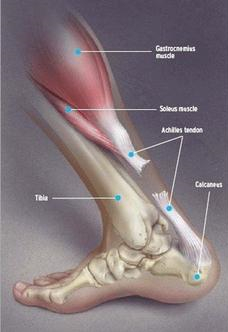

跟腱的解剖:

跟腱是人体最长、最强大的腱性组织之一,成人跟腱长越15cm,起始于小腿中部,止于跟骨结节后面的中点,由小腿三头肌肌腱合成。其在根骨止点上约4cm最窄而厚,向近端逐渐展开变宽变薄。

在跟腱中下部,即跟骨结节以上2~6cm处血液供应较差,跟腱营养不良,因而此处最容易发生断裂。